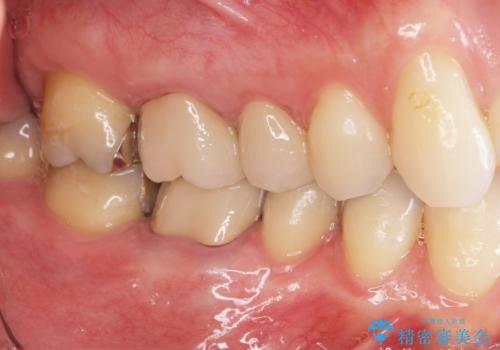

- 突き出た前歯の角度の改善と虫歯治療の改善を求めて来院されました。

虫歯を除去したのち、マウスピース矯正治療を行い、歯並びやがたつきを改善したのち、セラミックに置き換えることで審美性の向上を計画します。